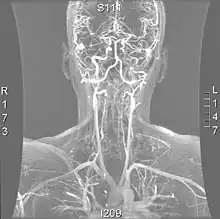

Angio MRI of supra-aortic vessels after the injection of 20cc of gadolinium for contrast

Magnetic resonance imaging has the ability to quantify the plaque anatomy and composition. This allows physicians to determine certain characteristics of the plaque such as how likely it is to break away from the wall and become an embolus. MRI does not use ionizing radiation, so the number of times that it is used on a single person is not a concern; however since it uses strong magnetic fields those who have metal implants cannot use this technique.[1][2]